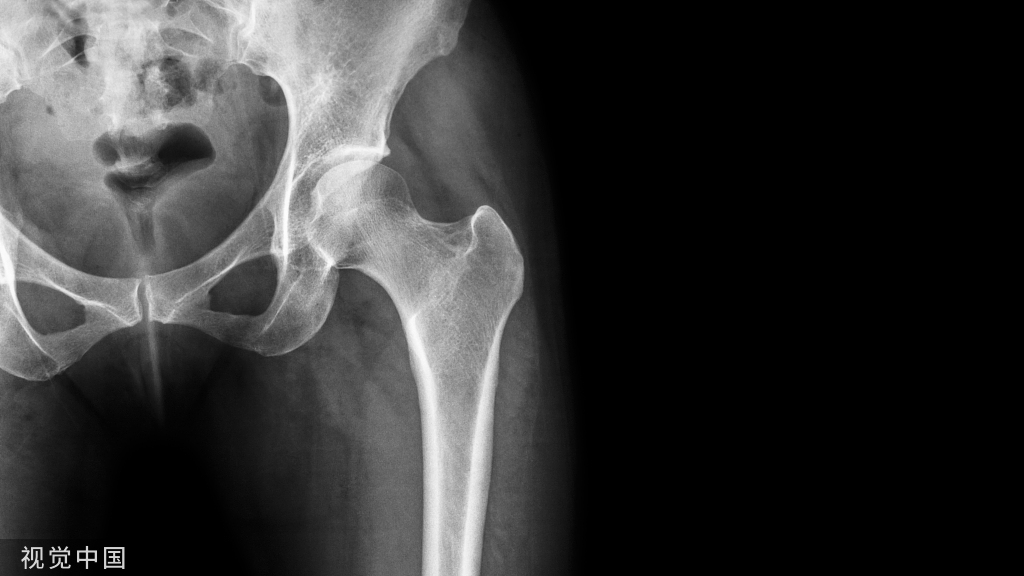

儿童股骨干骨折骨骨折

适用于5岁以下儿童有移位的股骨干骨折。伤侧、健侧同时用胶布皮牵引,双腿同时悬吊,臀部离开床面,牵引重量健侧比伤侧稍轻,为了防止成角畸形,可用夹板外固定。

水平皮肤牵引法

适用于5~12岁儿童有移位的股骨干骨折。股骨干中、上段横断、重叠骨折,在麻醉下进行整复、夹板外固定后,伤肢水平牵引,或用托马氏架牵引,重量2~3公斤。股骨上1/3骨折,伤肢应在充分屈髋,外展位牵引。股骨下1/3骨折,要尽量屈膝,以松弛膝后方的关节囊和腓肠肌,减少骨折远端向后侧的移位。胫、腓骨骨干双骨折